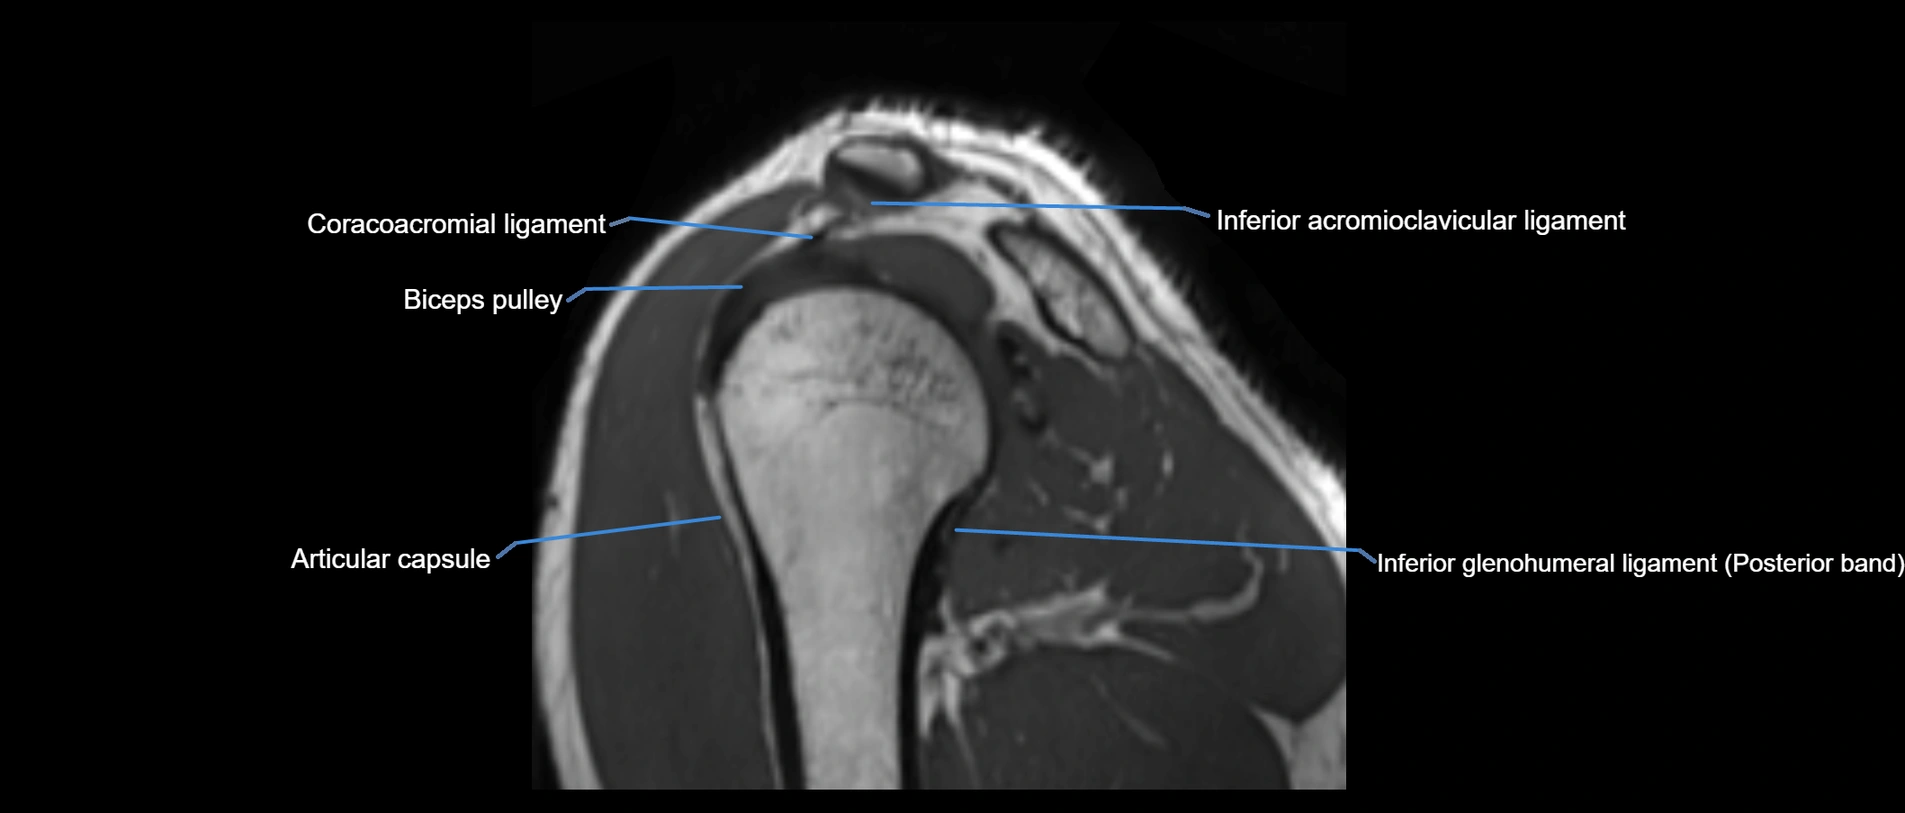

CT image

image